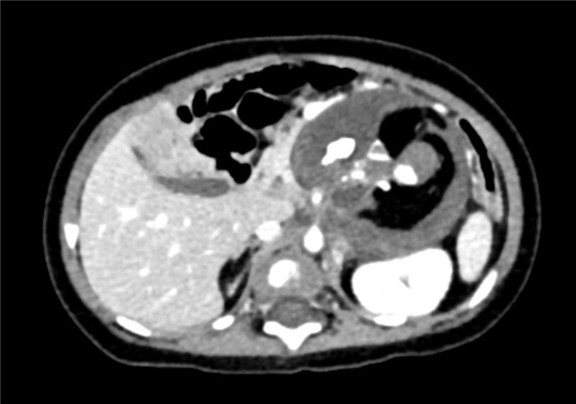

现病史:患儿于孕期26周体检时发现腹部囊实性肿块,大小约2.4*2.2cm,出生后密切关注患儿腹部情况,因腹部肿块逐渐增大于2017-08-10来我院门诊就诊,行腹部CT平扫检查发现胰腺下方见团块状低密度影,其内密度不均,可见脂肪密度影及钙质密度影,大小约8cm×5cm。出生后患儿无反酸、厌食、恶心、呕吐,无腹痛、腹泻、便秘等不适症状,今为行手术治疗来我院。

下腹部增强CT示:腹腔巨大占位,考虑畸胎瘤可能性大

术前CT检查: